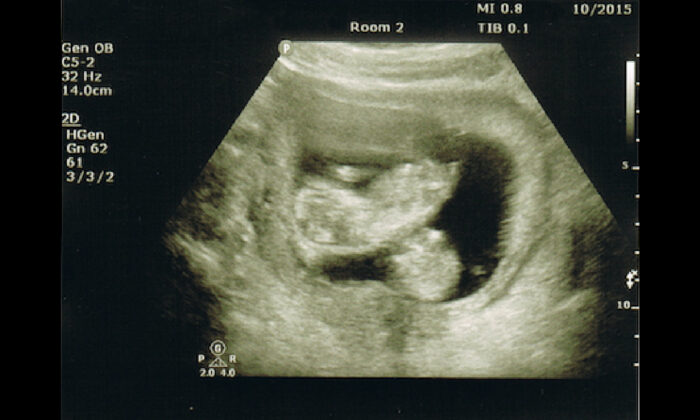

Les jumeaux apportent deux fois plus de joie aux parents, mais ces grossesses spéciales comportent aussi des risques plus grands. Pour une mère enceinte de Caroline du Nord qui avait des jumelles en route, une échographie à 20 semaines a révélé une maladie rare qui menaçait la vie de ses deux bébés.

Mais une surprise les attendait le lendemain, lorsqu’une échographie a révélé que le cœur des deux bébés battait normalement. « Le lendemain, nous avons été complètement époustouflés », se souvient le Dr Stephenson. Les Swanson croyaient qu’une puissance supérieure était à l’œuvre. « Dieu veillait sur nous », a dit Jeremy Swanson au WSOC.